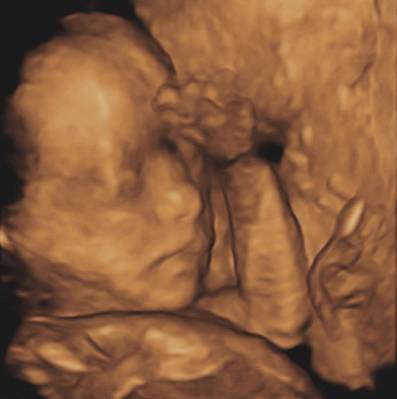

但是现在我能有什么照片,完全取决于我妈。说回正题,目前我最满意的照片是这张。

这小五官,这小气质,啧啧

感受到我那睥睨一切的神态没?有志不在年高,本宝宝出生后的宏愿可是——如未风云宇宙,当须雨露乡间!

这就是我心中的好照片。清晰,神态生动。(不过答到这里我突然发现,这两张照片还都不是我妈拍的,是医生给拍的。)